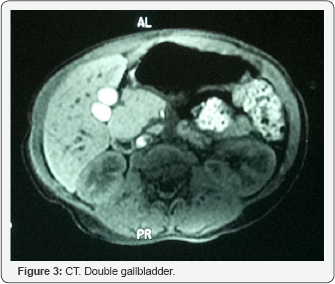

The diagnosis of annular pancreas has been confirmed during the laparothomy. In accordance with the pictures obtained during the upper gastrointestinal tract radiography, the duodenal obstruction was placed in the descending part of duodenum. A duodenoplasty (Heineke-Mikulicz type) was performed. As the bile flow during ERCP was completely undisturbed and the second duodenal papilla drained the pancreas the surgical intervention do not involved the gallbladder duplication or duplication of the duodenal papillas, due to the clinical irrelevance of these congenital malformations. The postoperative recovery was uneventful and the patient was discharged on the tenth day after surgery. No recurrence of gastrointestinal tract obstruction has been observed during the one year follow-up. The patient has the growth retardation due to the Noonan syndrome, but he has no more gastrointestinal symptoms (Figure 3).